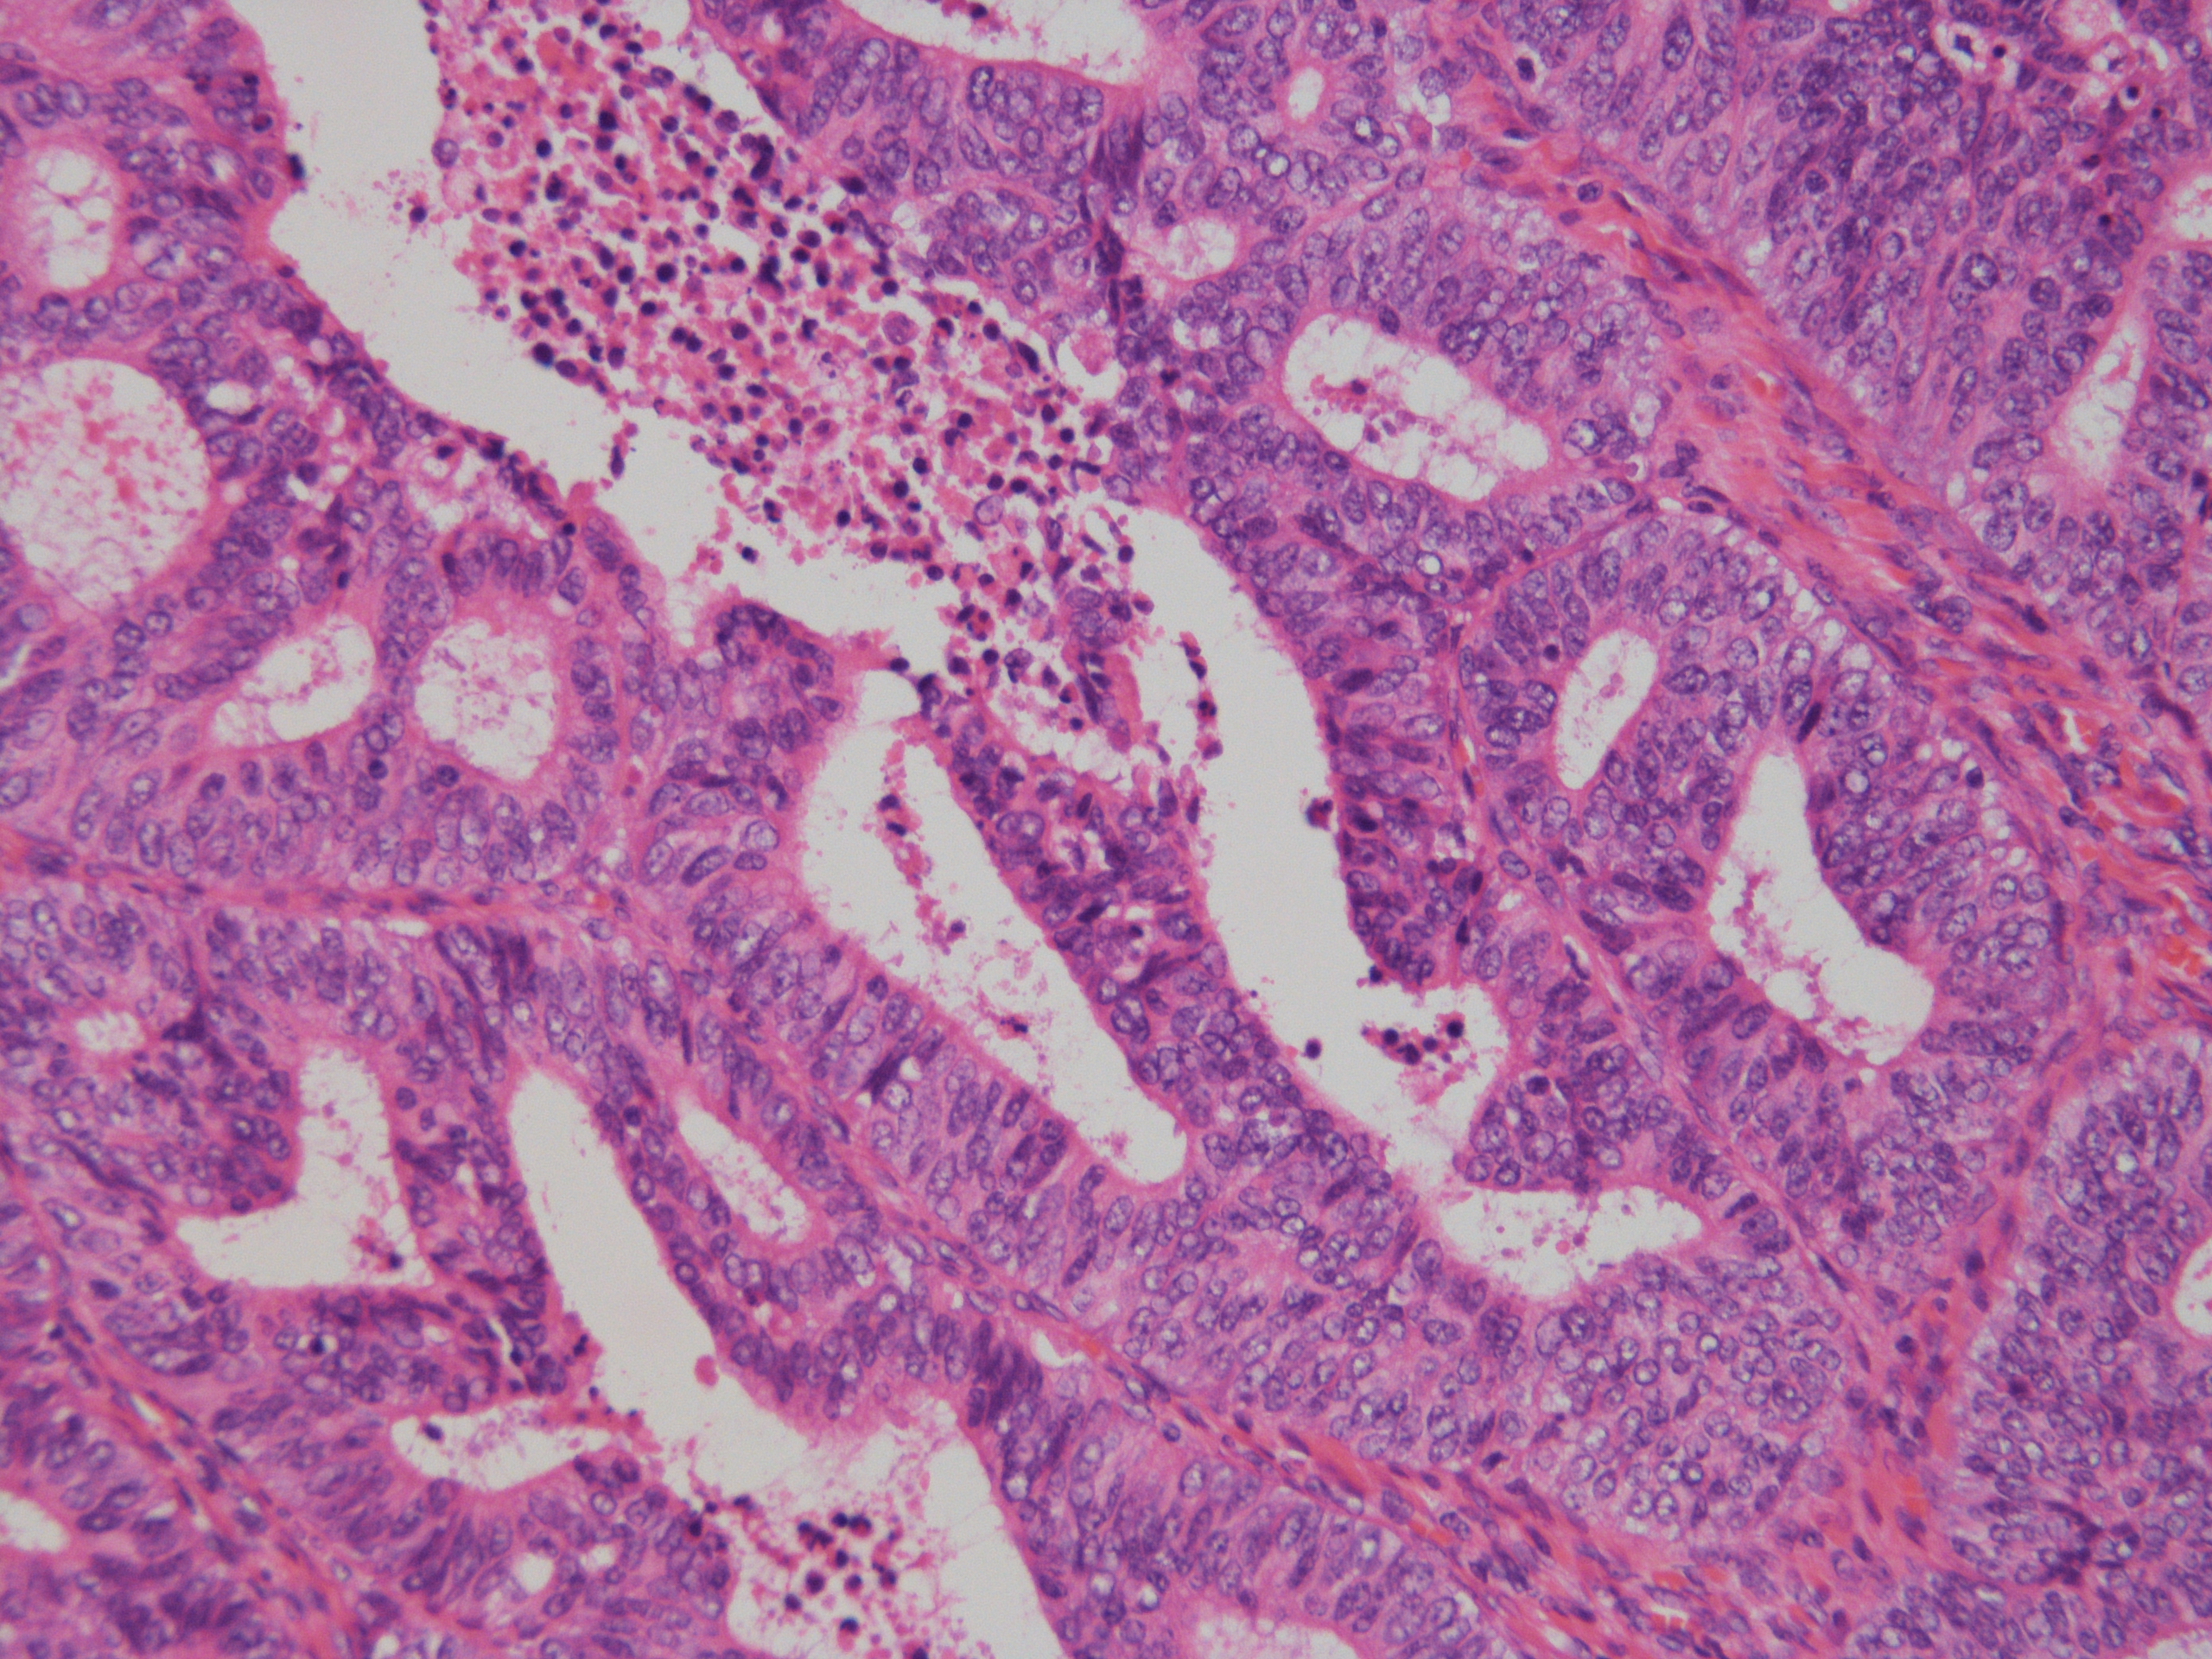

症例1解答、解説、討論記録

解答:類内膜癌(Grade1)

土管状集塊やシート集塊、大型組織様集塊、間質細胞集塊が出現している中に、不整突出集塊をわずかに認めた。

細胞診は、不整形突出集塊が単層で核異型に乏しいため「陰性」と判定したが、

手術標本(子宮摘出)の病理診断は類内膜癌(Grade1)で、手術標本と細胞診の所見に乖離を認めた。

渡辺先生より、細胞診の不整形突集塊は「手術標本で子宮内膜増殖症の所見も認められたので子宮内膜増殖症を見ている可能性がある」

とコメントを頂いた。